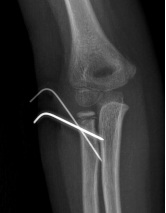

内固定

接骨板、螺钉

C:\Users\ADMINI~1\AppData\Local\Temp\ksohtml5168\wps19.png

髓内钉、克氏针

C:\Users\ADMINI~1\AppData\Local\Temp\ksohtml5168\wps20.pngC:\Users\ADMINI~1\AppData\Local\Temp\ksohtml5168\wps21.png